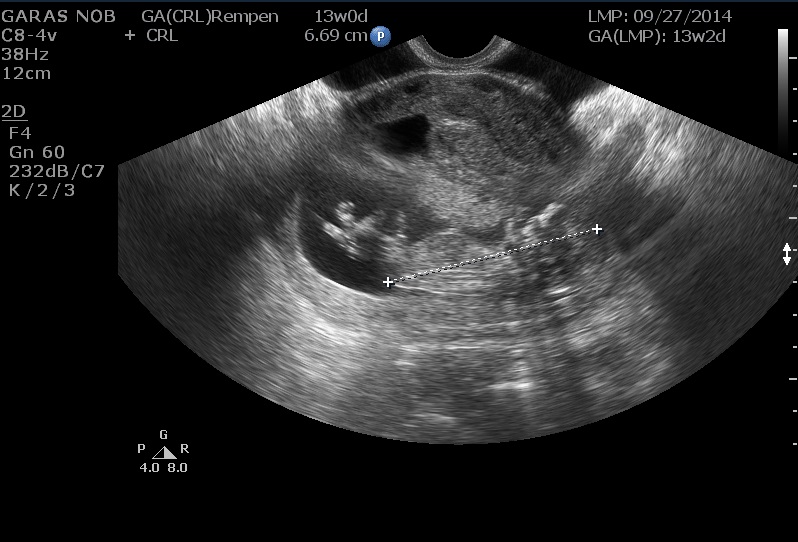

I posted my nub pictures about a week ago, but they were unclear. I thought I saw something! Anyway, I figured out how to post video I have from my ultrasound. I slowed it down because the original was only 4 seconds long. Between the legs of my baby, I think there is a moving nub? It looks different from our baby's legs which are crossed. Like a little stack, I wish I could circle it. Any ideas? I appreciate it!